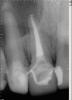

kenig Опубликовано 18 октября, 2012 Поделиться Опубликовано 18 октября, 2012 (изменено) Июль 12г.Жалобы:постоянный привкус гноя во рту, по утрам под губой белый сгусток, каждые три дня распухает небо, при нажатии на небо выделяется гной в области 12 зуба.Объективно:11 зуб покрыт исскуственной коронкой, 12 временная реставрация (находится на этапе лечения), 13 зуб интактный. В области 12 зуба с вестибулярной стороны свищ.R-гр.: киста вобласти 11,12,13 зубов.Анамнез: 12 зуб лечат год в другом лечебном учреждении, безуспешно, ничего не меняется.Рекомендовано:КТ верхней челюстиЭндо-лечение 11,12,13 зубов. Проведено лечение 11 зуба-коффердам, хлорка, лимонка, каласепт на две недели,пломбирование-вертикалка. Результат-пациент счастлив-привкус гноя пропал, под губой по утрам ничего нет, распухает раз внеделю. Свищ на месте. Проведено лечение 13 зуба-коффердам, хлорка, лимонка,каласепт на две недели, пломбирование-вертикалка. Все это время 12 зуб моем, моем,но из него все время льется, хотя через 10-20 минут мытья его возможно высушить.Результат-еще лучше, распухает раз в две недели. Свищ на месте..Сентябрь-наконец-то принесли КТ-ужас. В процессе небный корень 14 зуба, хотя реагирует на холод как витальный зуб. Небно нет кости от 11 до 14 зуба, в области 11 зуба сообщение с полостью носа. Вопросы:Эндо 14 зубу проводить? Реагирует на холод, как живой.12 зуб пломбировать? Просушить его возможно через минут 10-20 мытья. Временные промежутки между обострениями увеличиваются, но меня результат не радует.Как бы поступили Вы в такой клинической ситуации? -диагностический 12 зуба-контрольный 11 зуба-контрольный 13 зуба-КТ 11 зуба-КТ 12 зуба-КТ 13 зуба-КТ 14 зуба был подобный случай, причинный был 22, эндо с апексификацией 22, гидроокись не приносила ожидаемых результатов, раз 5 получал несколько 2-кубовых шприца желтой опалесцирующей жидкости, потом высушил, запаковал МТА, хоирург сделал декомпрессию по парч, полтора года мыли хлоргексидином раз в 2 недели, вот что получилось, без всякой хирургии Изменено 18 октября, 2012 пользователем kenig 1 Ссылка на комментарий